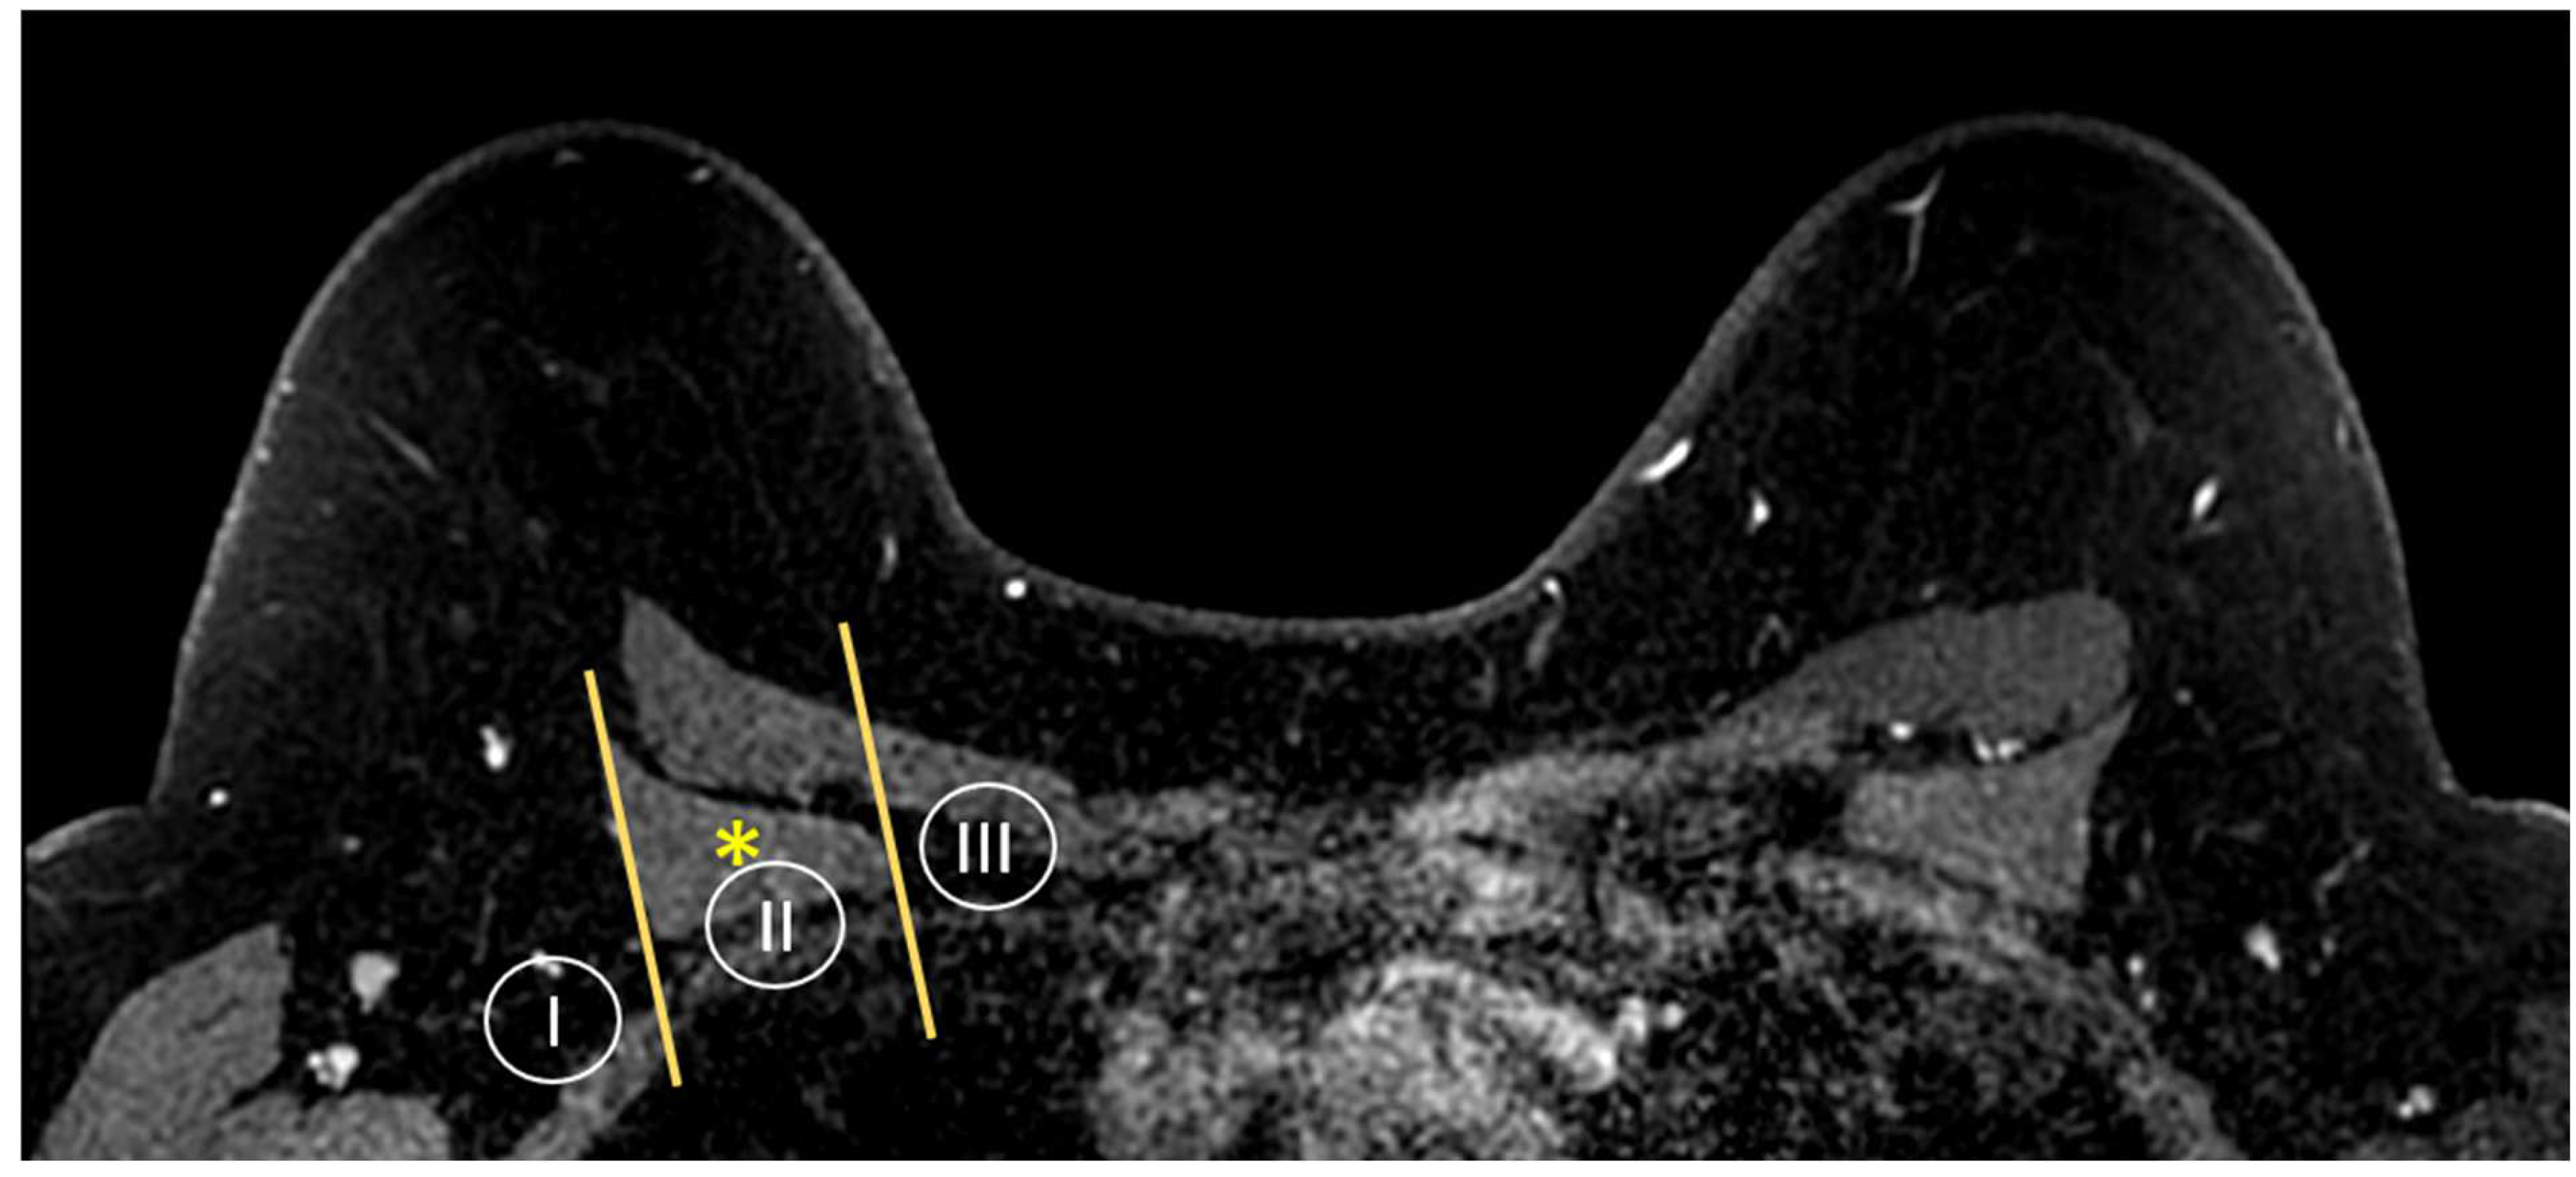

MR imaging is also able to provide a global view of the axillary and internal mammary nodal stations (Figure 5 and Figure 6). Axillary lymph nodes are divided into levels I, II, and III. The levels are defined by the relationship of the lymph node to the pectoralis minor muscle. Level I lymph nodes are inferolateral to the pectoralis minor; level II lymph nodes are posterior to and between the lateral and medial borders of the pectoralis minor; and level III lymph nodes are superomedial to the pectoralis minor [36]. Internal mammary lymph nodes (IMLN) are typically visualized in the first through sixth intercostal spaces.

Figure 5.

Anatomy of the axillary nodal stations on axial T1W fat-suppressed post-contrast breast MRI. Levels are defined by the relationship of the lymph node to the pectoralis minor muscle (asterisk).

Figure 6.

Axial T1W fat-suppressed post-contrast breast MRI provides a global view of the axillary and internal mammary nodal basins. In this case, level I axillary adenopathy (asterisk) and internal mammary adenopathy (arrowhead) are present.